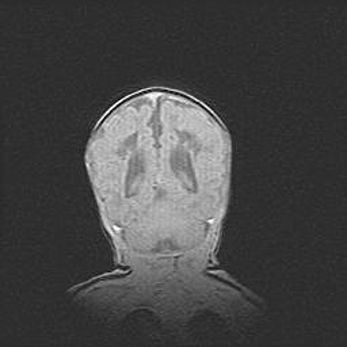

Лейкомаляция с кистозно-глиозной дегенерацией головного мозга.

Возраст: 2 месяца 25 дней

Вес: 6400 г

Окружность головы: 40 см

Срок гестации: 41 неделя

Лейкомаляцию относят к ишемически-гипоксическим повреждениям головного мозга, диагностируемым у новорожденных. При лейкомаляции в головном мозге обнаруживают очаги некроза, возникшие после тяжелой гипоксии и нарушения кровотока. В процессе морфогенеза очаги проходят три стадии: 1) развития некроза, 2) резорбции и 3) формирования глиозного рубца или кисты. Перивентрикулярная лейкомаляция (ПЛ) встречается примерно в 12% случаев среди новорожденных, обычно – у недоношенных детей, причем, частота ее зависит от массы, с которой младенец появился на свет. Наибольшее число малышей страдает лейкомаляцией, если масса при рождении 1500-2500 г.